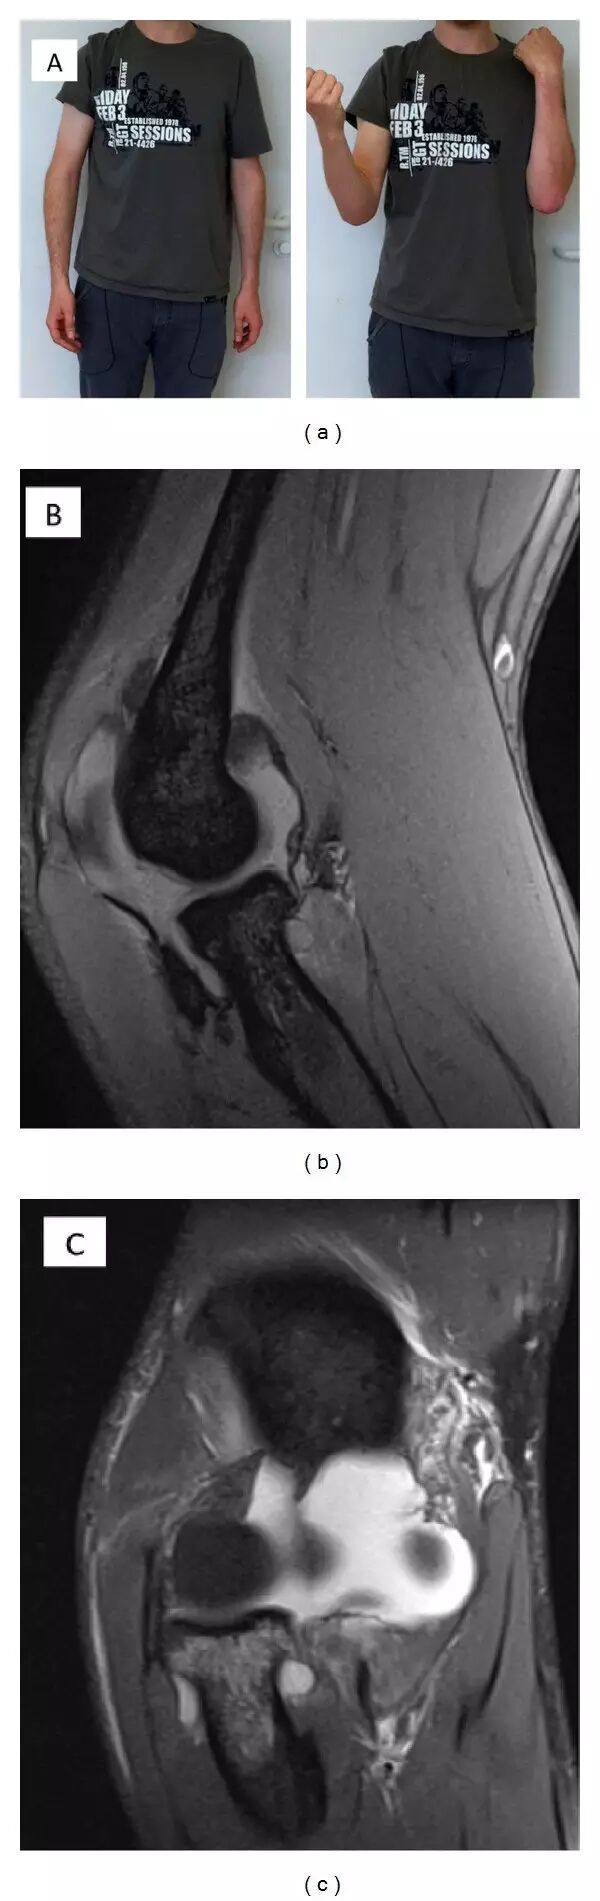

大多数关于单个MUCL病变的知识已经从检查运动员例如标枪投掷者或手球运动员获得[41]。 慢性不稳定性需要手术包括韧带增大[42]。 在我们的经验中,具有外翻应力损伤和连续单个MUCL病变的急性创伤患者受到有限的运动范围的困扰(图5(a))。 肘的二维X射线图像通常不显示具有规则对准的骨折。 MRI在这种情况下说明单个MUCL损伤(图5(b)-5(c))。 然而,如果他们试图这样做,则不能弯曲他们的肘的患者通常是疼痛的。 患者倾向于伸展其肘,并排斥高于80°的任何屈曲,这是MUCL变形或破裂的强临床标志。 在屈曲运动的有限范围内支撑肘部将在2至4周内或在严重情况下至多8周导致无疼痛的稳定肘部。

(a)通过外翻应力创伤的前内侧尺骨副韧带(aMUCL)的分离的破裂。 患者通常在屈曲时受到有限范围的运动。 创伤后10周,用保守治疗恢复具有稳定肘的全范围运动。 (b)MRI检查分离的aMUCL断裂的拍照患者。 矢状面示出炎症反应。 (c)额状面显示MUCL复合体从其在内髁上肱骨近端插入的破裂。